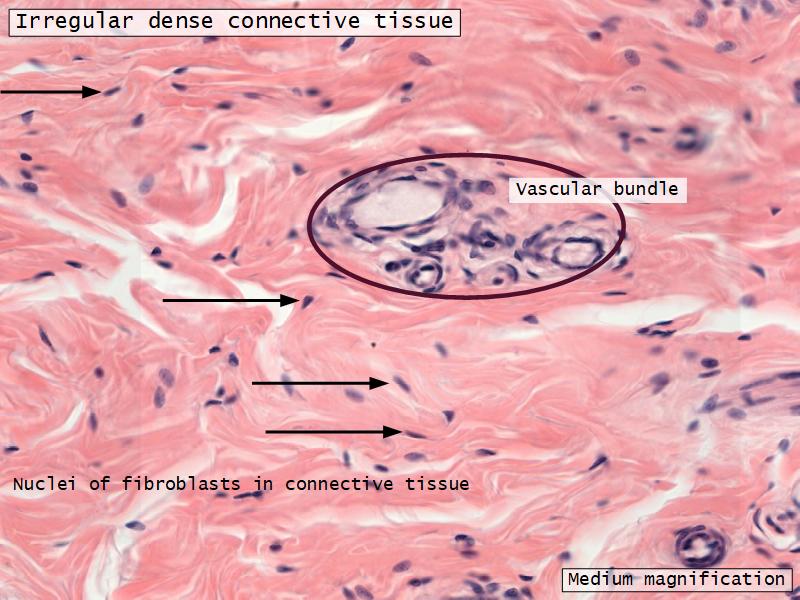

Stroma

- Collagenous connective tissue

- Irregular dense connective tissue

- Smooth muscle

- Fibres and bundles

- Lactiferous sinusses

- Stratified cuboidal epithelium